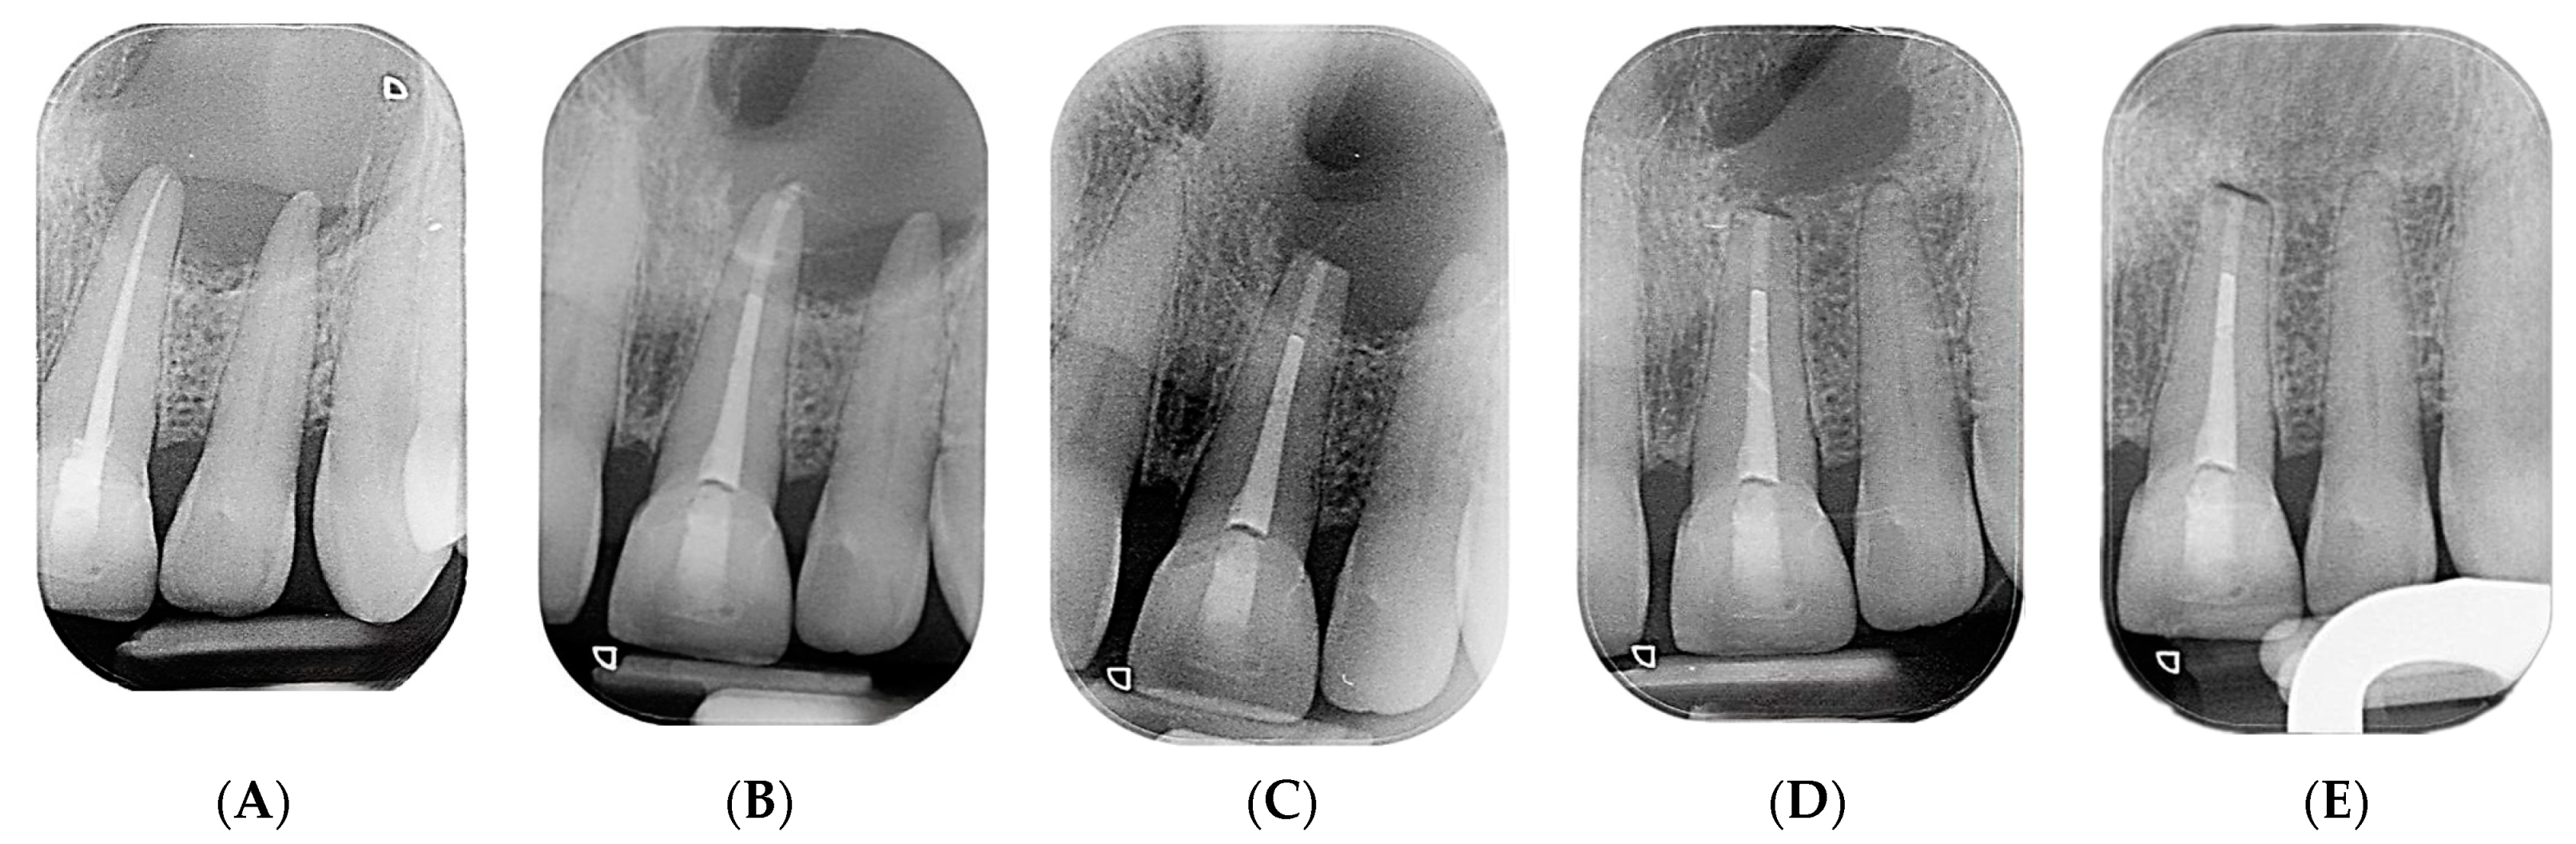

2. Case Presentation

2.1. Chief Complaints History and Clinical Findings

2.2. Delivery of Treatment

2.4. Healing of the Defect and Follow Up